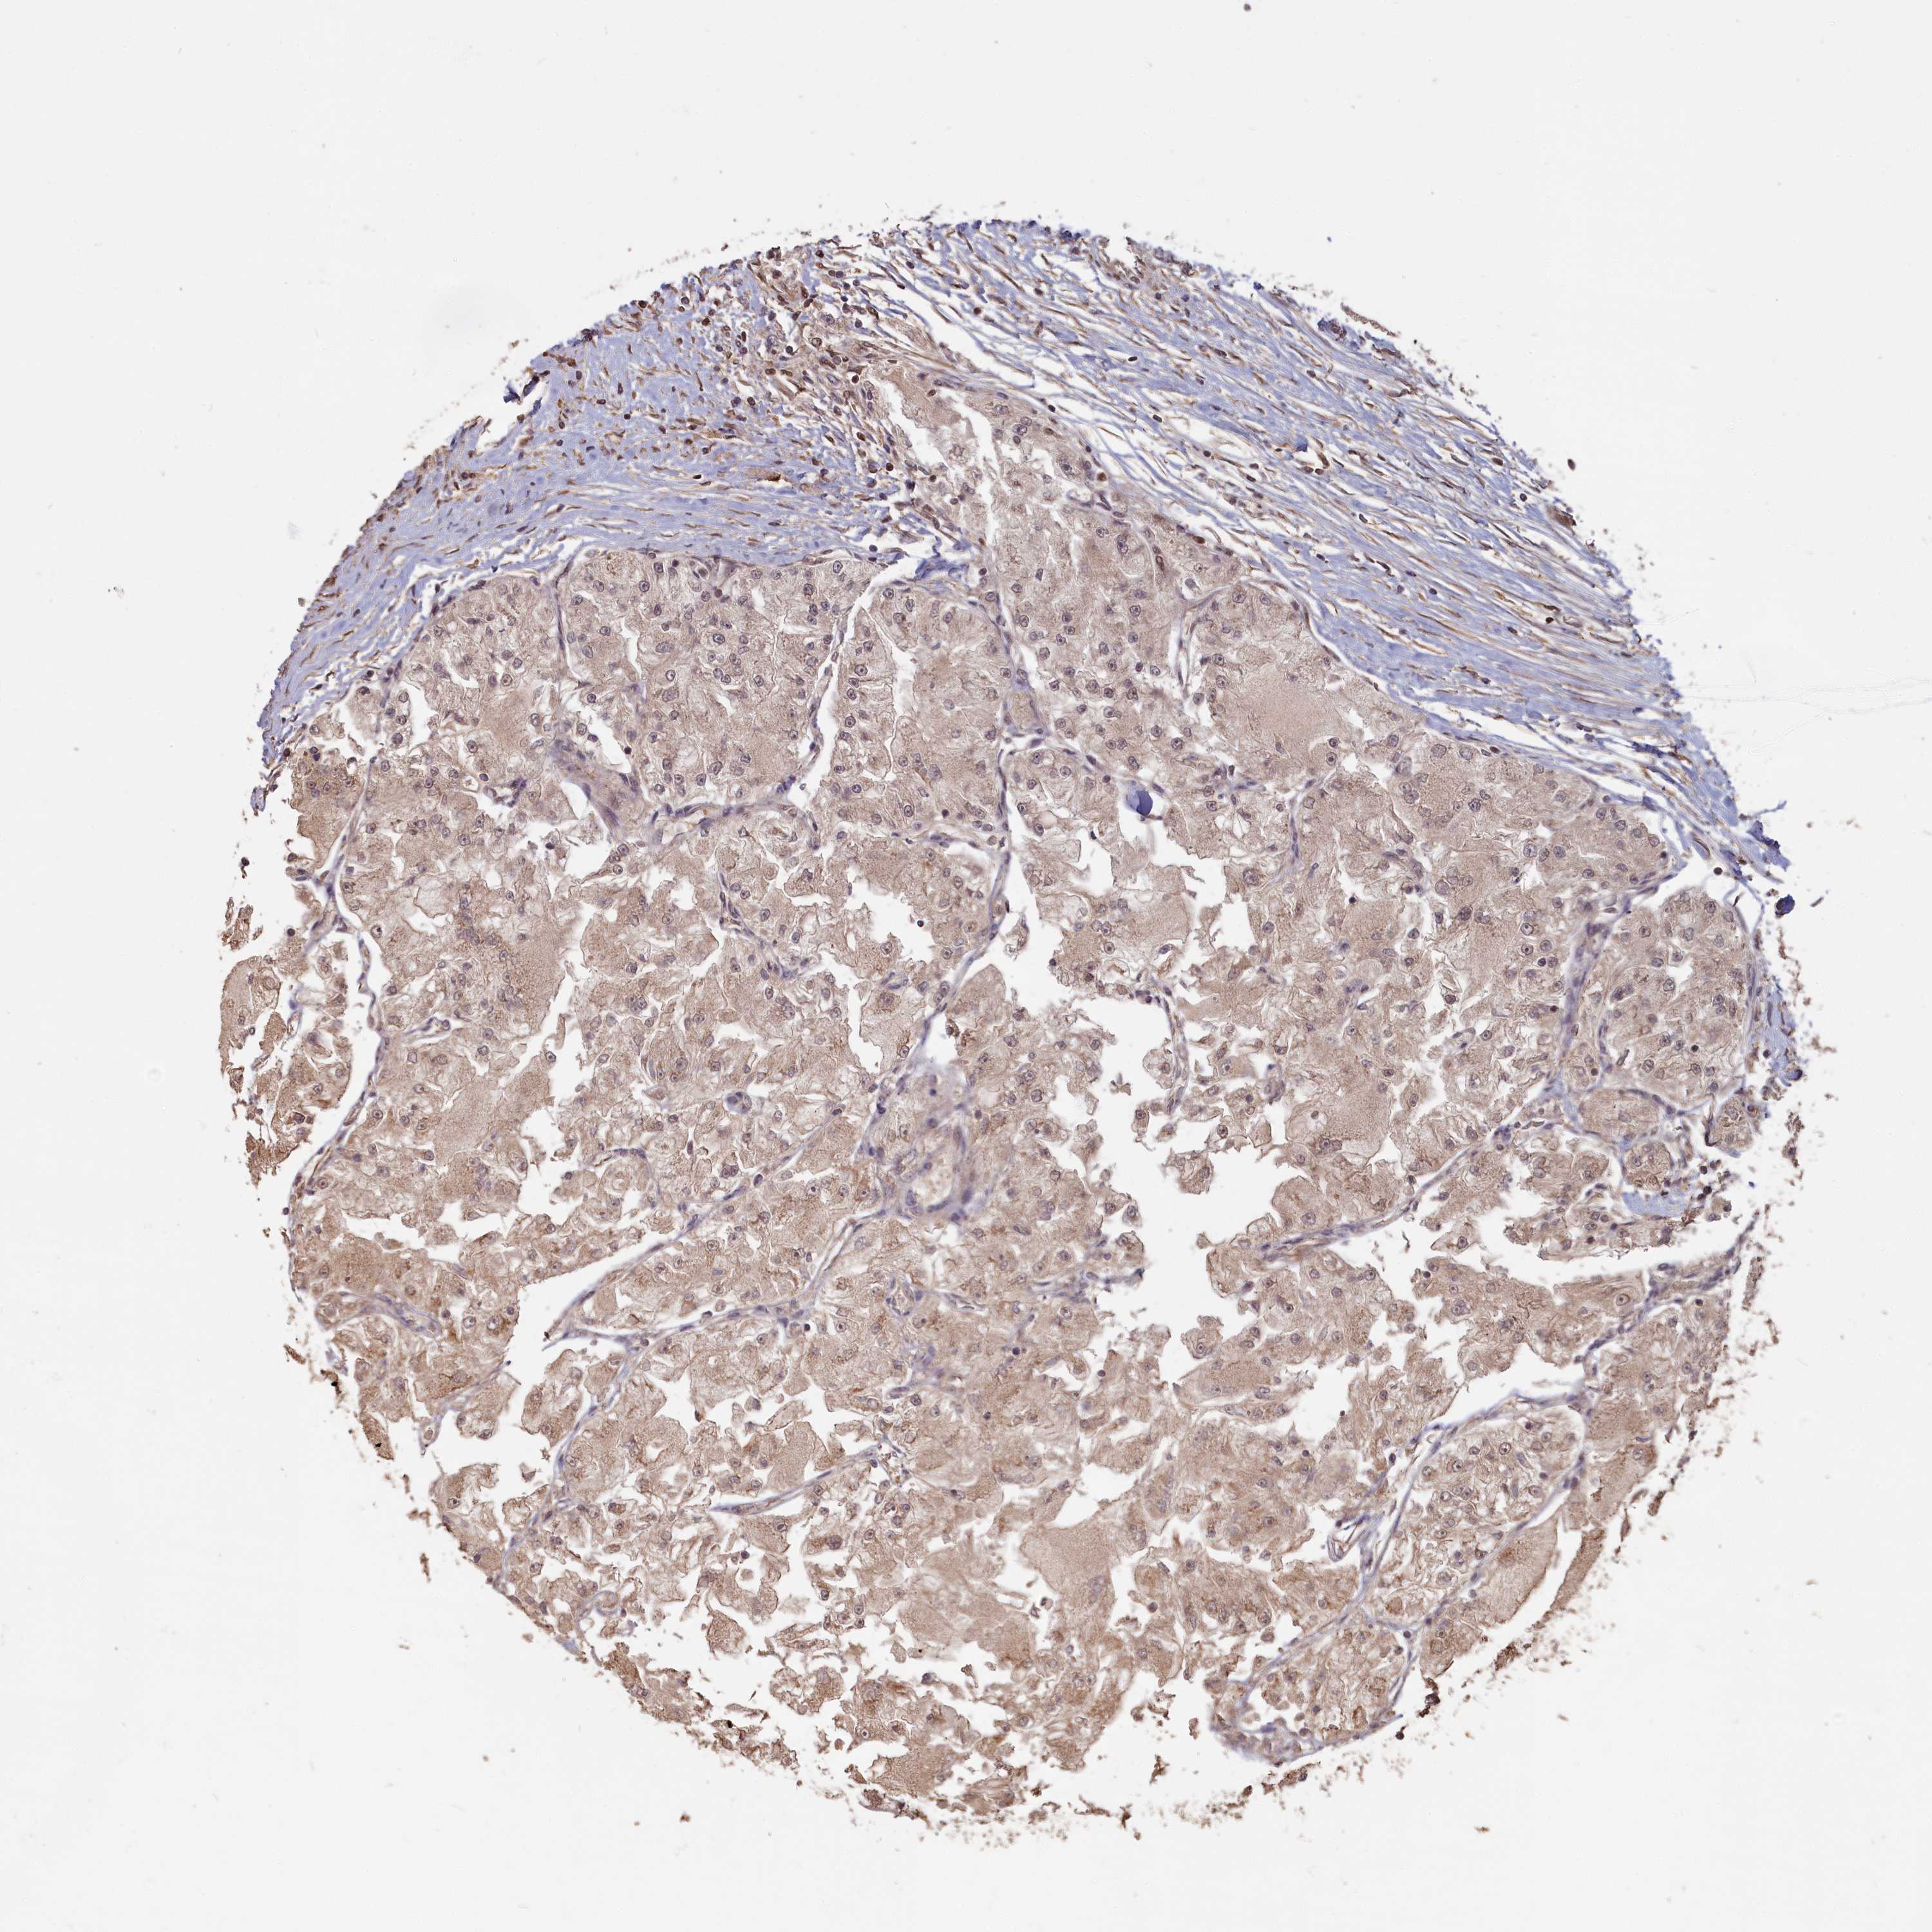

KIDNEY RENAL CLEAR CELL CARCINOMA (VALIDATION) - Interactive survival scatter ploti

The Survival Scatter plot shows the clinical status (i.e. dead or alive) for all individuals in the patient cohort, based on the same data that underlies the corresponding Kaplan-Meier plots. Patients that are alive at last time for follow-up are shown in blue and patients who have died during the study are shown in red.

The x-axis shows the expression levels (FPKM) of the investigated gene in the tumor tissue at the time of diagnosis. The y-axis shows the follow-up time after diagnosis (years). Both axes are complimented with kernel density curves demonstrating the data density over the axes. The top density plot shows the expression levels (FPKM) distribution among dead (red) and alive patients (blue). The right density plot shows the data density of the survived years of dead patients with high and low expression levels respectively, stratified using the cutoff indicated by the vertical dashed line through the Survival Scatter plot. This cutoff is automatically defined based on the FPKM cutoff that minimizes the p-score. The cutoff can be changed by dragging the vertical line or by entering a cutoff value in the square labeled "Current cut-off".

Under the Survival Scatter plot the p-score landscape (black curve; left axis) is shown together with dead median separation (red curve; right axis). Dead median separation is the difference in median mRNA expression between patients who have died with high and low expression, respectively. It is calculated as follows: median FPKM expression of dead patients with high expression - median FPKM expression of dead patients with low expression. This is intended to aid the user in visually exploring custom cutoffs and the associated p-scores and dead median separation.

Individual patient data is displayed and can be filtered by clicking on one or more of the category buttons on the top of the page. Categories describing expression level and patient information include: high, low, alive, dead, female, male and tumor stages. The scale of the x-axis can be toggled between linear and log-scale by clicking on the "x log" button. Mouse-over function shows TCGA ID, patient information and mRNA expression (FPKM) for each patient.

& Survival analysisi

Kaplan-Meier plots summarize results from analysis of correlation between mRNA expression level and patient survival. Patients were divided based on level of expression into one of the two groups "low" (under cut off) or "high" (over cut off). X-axis shows time for survival (years) and y-axis shows the probability of survival, where 1.0 corresponds to 100 percent.

HIF3A is not prognostic in Kidney Renal Clear Cell Carcinoma (validation)

Best expression cut offi

Based on the FPKM value of each gene, patients were classified into two groups and association between prognosis (survival) and gene expression (FPKM) was examined. The best expression cut-off refers the FPKM value that yields maximal difference with regard to survival between the two groups at the lowest log-rank P-value. Best expression cut-off was selected based on survival analysis .

When clicking on this number, the vertical dashed line indicating cut-off, the interactive survival plot, and the Kaplan-Meier curve will be adjusted to show results based on the best expression cut-off.

: 2.27

P scorei

Log-rank P value for Kaplan-Meier plot showing results from analysis of correlation between mRNA expression level and patient survival.

N/A

5-year survival highi

5-year survival for patients with higher expression than the expression cutoff.

For melanoma and glioma, 3-year survival is shown.

5-year survival lowi

5-year survival for patients with lower expression than the expression cutoff.

TCGA RNA samplesi

RNA-seq data is reported as average FPKM (number Fragments Per Kilobase of exon per Million reads), generated by the The Cancer Genome Atlas (TCGA) .

Normal distribution across the dataset is visualized with box plots, shown as median and 25th and 75th percentiles. Points are displayed as outliers if they are above or below 1.5 times the interquartile range. FPKM values of the individual samples are presented next to the box plot.

Average pTPM 1.9

Number of samples 100